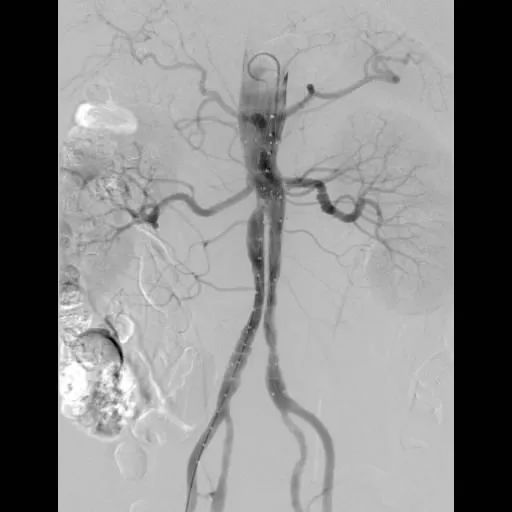

术后造影显示腹主动脉瘤消失,各分支内脏动脉显影良好,无内漏,表明手术成功